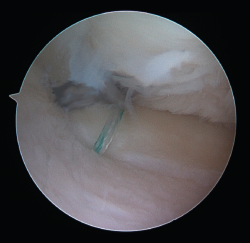

Figure 6. View from the anterolateral portal of the intraarticular positioning of the guide and the intraarticular exit of the tunnels at the footprint of the posterior root of the internal meniscus of a right knee.

One of the patients in the standard guide group required modification of the perforation secondary to intraarticular exit of the Kirschner wire in a position different from that planned, due to positioning difficulties caused by the existence of a narrow intercondylar groove and prominent spines. The 3D printed guides adapted on both supports to the bone surface of the tibia and were precise in conducting the guide needles towards the planned position (Figures 6 and 7). There were no problems derived from friction between the metal of the needles and the bore of the customized guide, and handling was ergonomically satisfactory for the surgeon.